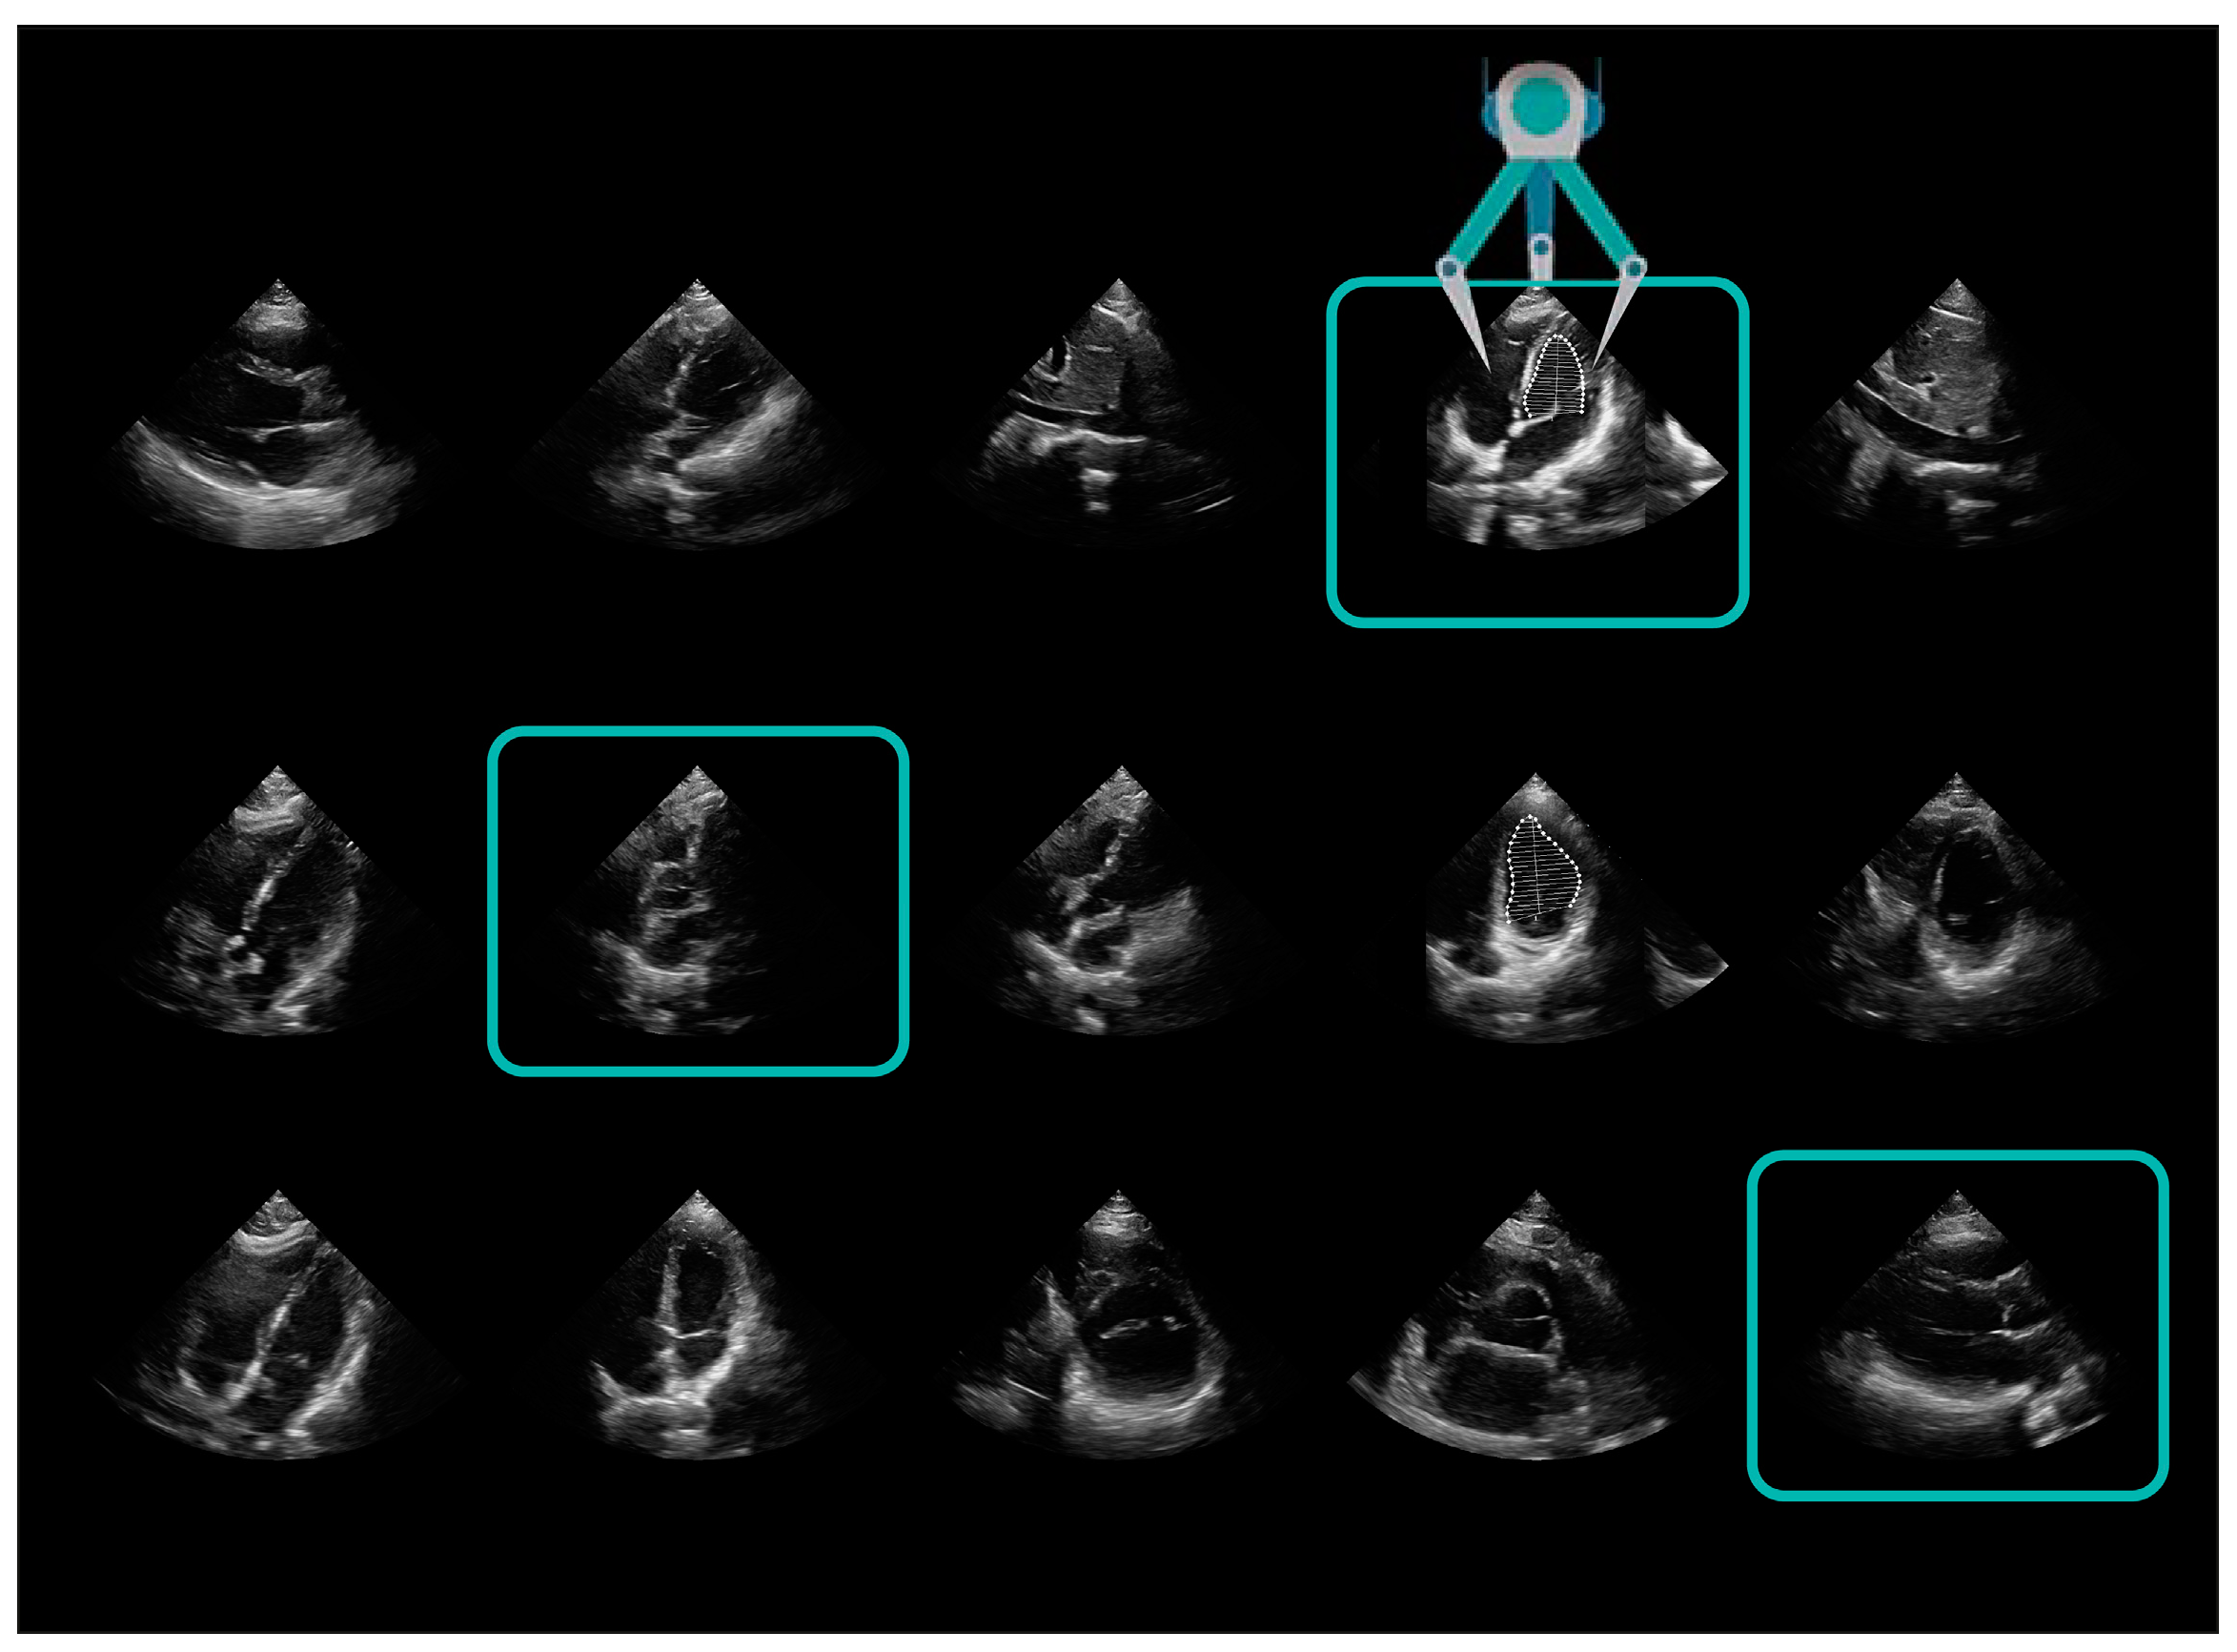

| AutoEF | Mindray | calculation of ejection fraction (EF) | Ultrasonographic assessment of cardiac function |

| RealTimeEF | GE | ||

| US2.AI | EchoNous | ||

| LvivoEF | Philips | ||